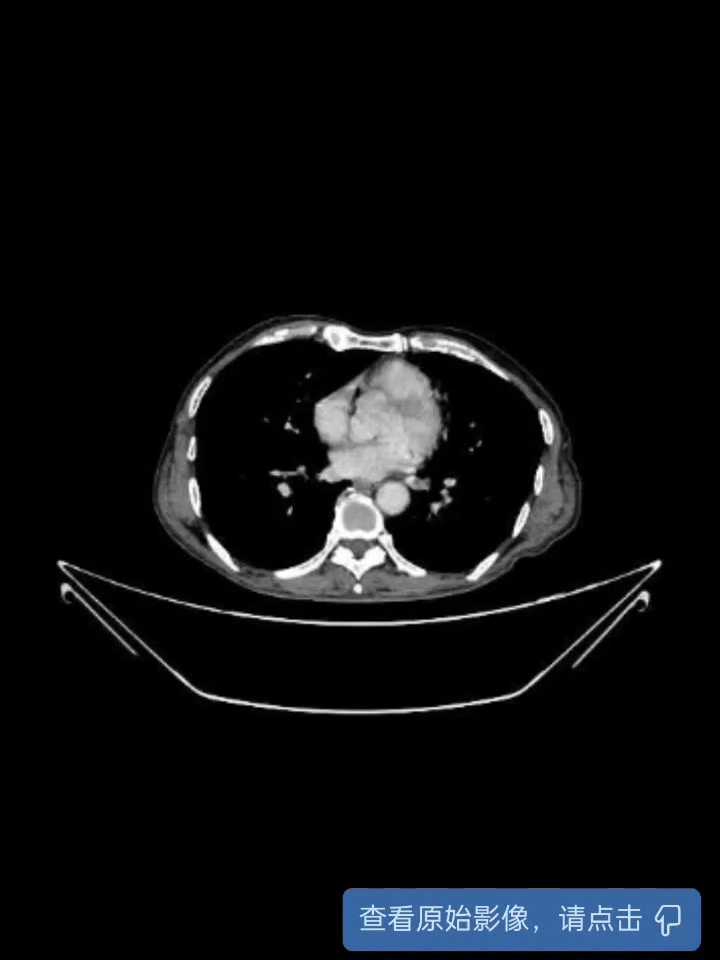

【检查】:下腹部CT平扫:1、扫及回盲部肠壁增厚伴周围渗出、淋巴结肿大,建议完善盆腔CT及进一步检查。2、右肾上腺多发钙化灶。3、腹主动脉及双侧髂动脉硬化。胃镜示:1、十二指肠球部溃疡(S2期)伴狭窄;2、慢性非萎缩性胃炎肠镜示:1、回盲部占位:Ca?;2、内痔。病理检查:“回盲部”低分化腺癌。

【临床诊断】:1、回盲部腺癌2、十二指肠球部溃疡伴狭窄3、慢性非萎缩性胃炎4、食管炎5、内痔。

【治疗经过及结果】: 入院后行抑制胃酸分泌,解痉止痛 ,调节胃肠道功能,康复新液促进黏膜修复,枸橼酸铋钾片保护胃粘膜,枸橼酸莫沙必利片促进胃肠蠕动,患者腹痛好转后行腹腔镜辅助右半结肠切除术+肠粘连松解术+右侧结肠旁沟、吻合口处引流术。术中游离肿瘤与后腹膜粘连过程中肿瘤破裂,且残留肿瘤组织与后腹膜、生殖血管粘连紧密,切除残留肿瘤组织、受侵犯生殖血管及受侵犯腰大肌组织。